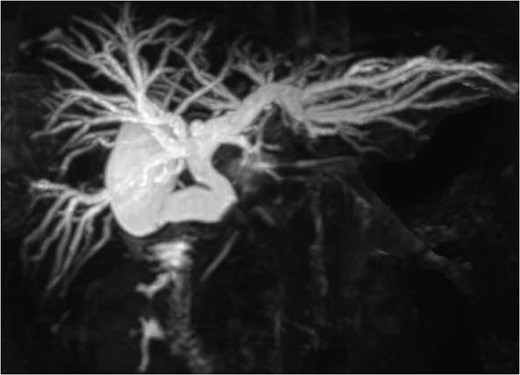

A 36-year-old woman was admitted to our hospital due to appetite loss, nausea, and back pain. A physical examination disclosed right hypochondriac tenderness and obvious jaundice. Laboratory studies showed elevated levels of total bilirubin (9.7 mg/dl), direct reacting bilirubin (6.0 mg/dl), aminotransferase (AST 281 U/l, ALT 362 U/l), alkaline phosphatase (1945 U/l,) and γ-glutamyltransferase (1769 U/l); however, her white blood cell count and C-reactive protein level were within the normal ranges. Magnetic resonance cholangiography revealed that the intrahepatic and common hepatic bile ducts were dilated, and that the gallbladder was distended (Fig. 1). Endoscopic retrograde cholangiography demonstrated a round-shaped filling defect at the confluence of the bile duct (Fig. 2). Based on the findings, the patient was diagnosed with Mirizzi syndrome Type II according to the Csendes classification [1]. Although, the endoscopic removal of the impacted gallstone was unsuccessful, a stent tube was placed for endoscopic retrograde biliary drainage in order to improve the patient’s obstructive jaundice. We planned to perform laparoscopic surgery.

Magnetic resonance cholangiography showed the dilated intrahepatic biliary tree, the common hepatic duct and the gallbladder.